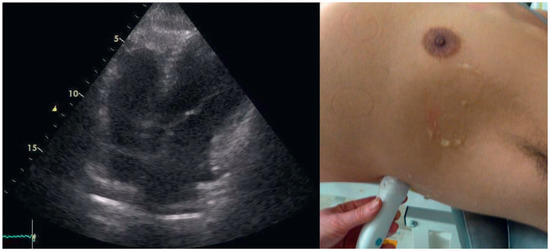

When Apical Is Parasternal, Or "Where Is the Heart?"

by Thilo Burkard and Beat A. Kaufmann

Cardiovasc. Med. 2015, 18(7-8), 226; https://doi.org/10.4414/cvm.2015.00345 - 12 Aug 2015

Viewed by 147

Abstract

A 57-year-old male presented to the medical outpatient department with typical angina pectoris Canadian Cardiovascular Society (CCS) class II and dyspnoea on exertion during the previous weeks [...] Full article

Show Figures

Figure 1